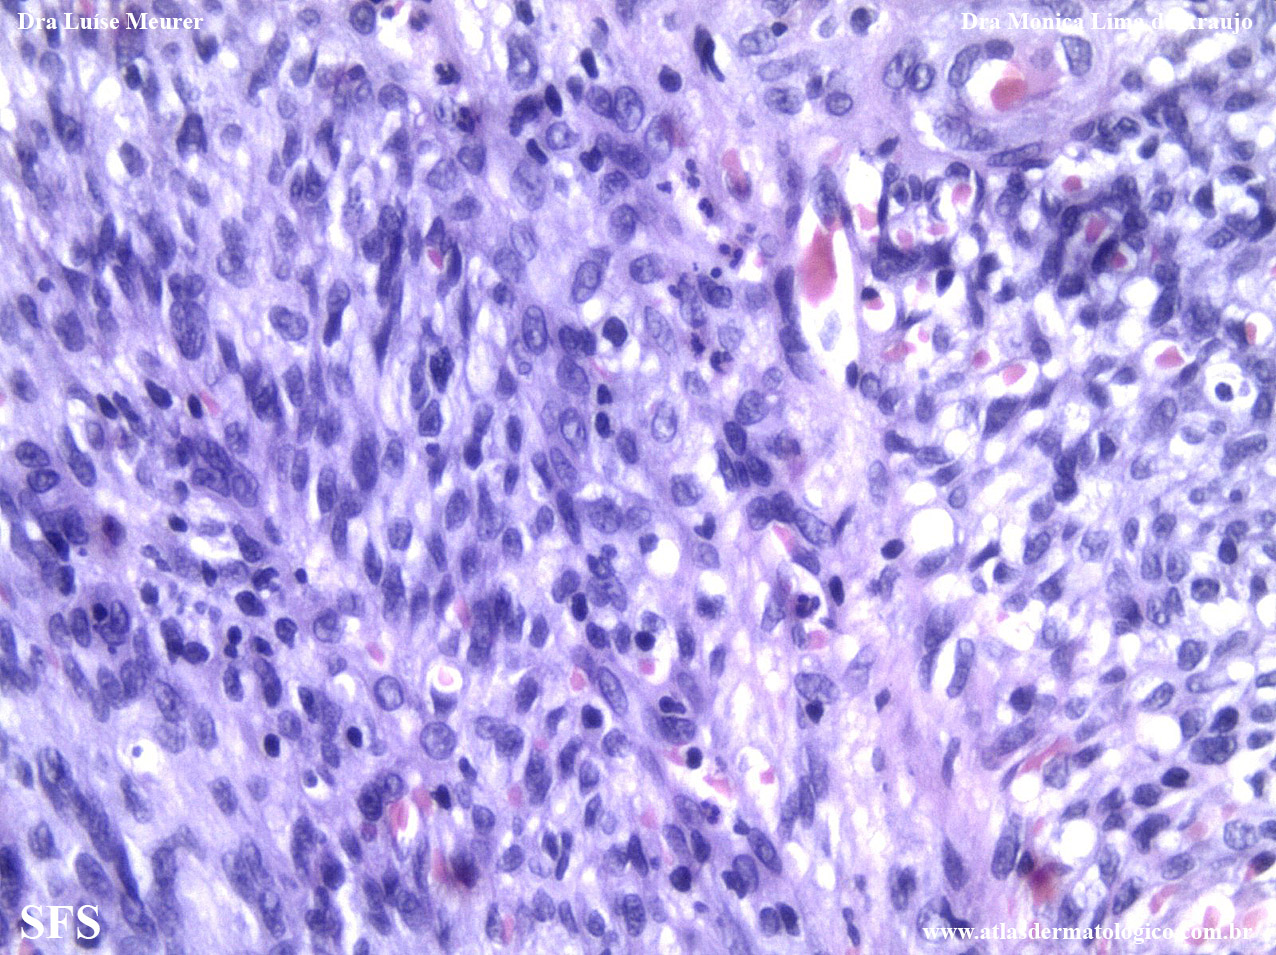

kaposi's _sarcoma_associated_herpesvirus_type_8